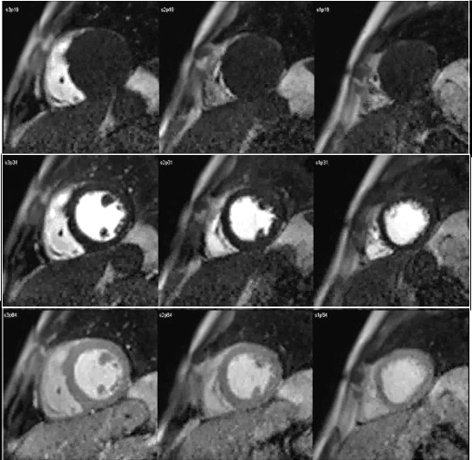

Perfusion defects in different territories can be detected in case of multivessel disease (Fig. 7) and, in patients with severe 3-vessel CAD, the perfusion study may show a global, intense, persistent defect which is readily recognizable (Fig. 8).

Fig. 8.Three-vessel perfusion defect. Stress and rest studies in a patient with severe left main and 3-vessel CAD (arrows, on the right panels) showing an inducible perfusion defect in most, if not all, of the myocardial segments during vasodilatory stress.